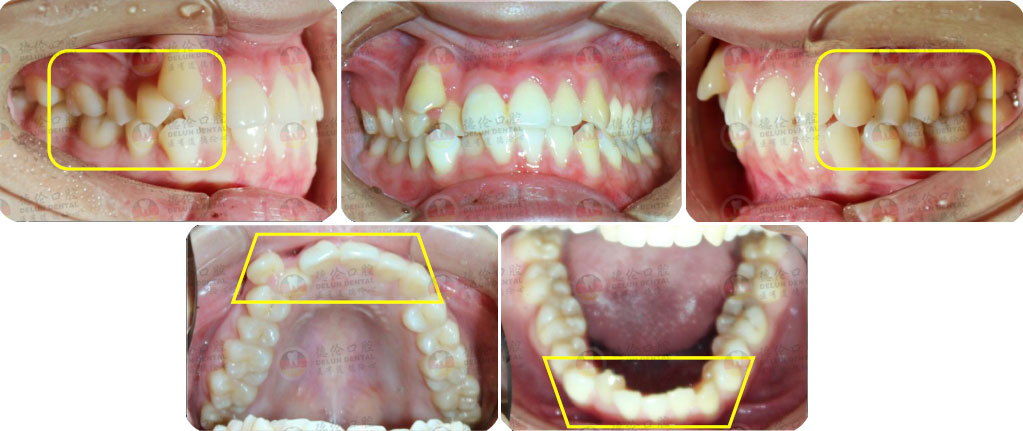

矯治采用兩種不同的厚度的膜片(牙套),發揮兩種不同膜片的各自優勢,在有效的作用時間內,矯治效率、矯治目標達成和舒適度方面較普通隱形矯正方式有明顯提升。

厚薄兩種矯治器,每周替換有利于牙齒位置的準確控制